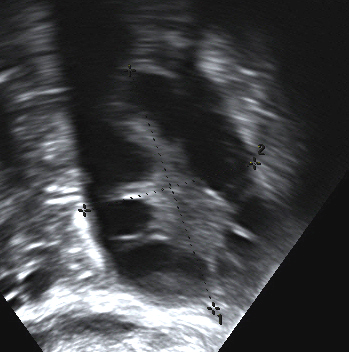

Particularly in the early stages of pregnancy, bleeding into the corpus luteum can cause a hemorrhagic corpus luteal cyst.